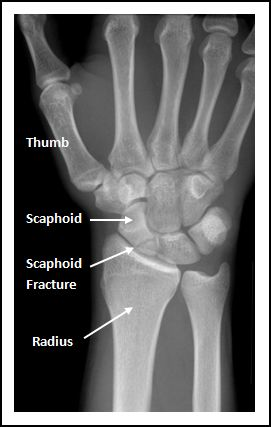

left scaphoid fracture

pain in the anatomical snuffbox → median nerve damage

numbness in the radial three digits of the hand